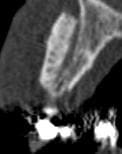

Je me permets de vous soumettre les clichés de scan à 5 mois d'une greffe d'apposition maxillaire antérieure secteur 11 12 que j'ai réalisée.

J'avoue avoir été surprise du hiatus qui existe encore entre greffon et os cortical initial, je suis d'ailleurs déçue je pensais que la forme que j'avais donnée permettait un meilleur "placage" du dit greffon.

D'après vous est ce que cette image est trop précoce dans le processus de cica et que mon "vide" va se combler dans les semainesà venir? je note bien l'intégration sur la crête et les bordures de la greffe.

ta 5 em coupe est pas si mal

sur la coupe 1 et 2 on percoit encore la corticale presqu'intact... on doit enclaver le bloc donneur dans l'os receveur

Il faut un contact intime du greffon avec le site receveur et ici cela ne devait pas être le cas sur toute la surface. Mais une partie semble bien minéralisée. Attends encore un mois avant d'intervenir, tu verras bien à ce moment là.

Je dois dire que quand j'ai reçu les images du scan j'ai fait défilé les coupes horizontales de cervical en apical et là j'étais ravie : on ne voyait cette maladaptation que dans une faible zone au tiers apical dans le creux de la concavité de 13. C'est après que j'ai déchanté.

Quand je fais circuler ma souris sur le logiciel de planification sur les zones "sombres" le logiciel m'indique une densité assez correcte très proche de celle de l'os spongieux du patient,du coup je me dis que la minéralisation est en cours....

Pourtant à partir de la coupe 142 on commence à voir une belle fusion entre les 2 surfaces.